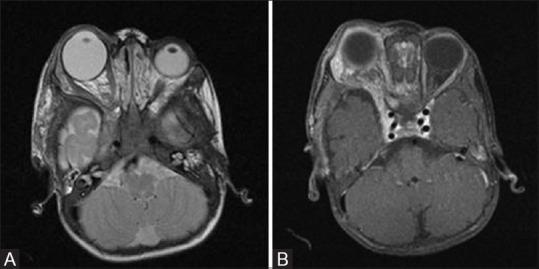

Phakomatoses or Neurocutaneous syndromes are a heterogeneous group of disorders and have variable inheritance pattern. Currently, more than 30 entities are included in this group. These disorders primarily affect the central nervous system; however, skin, viscera, and other connective tissues can also be involved with variable clinical presentation. We will describe and illustrate the various radiological findings of the common entities through the iconography of the cases presented to our department.

phakomatoses或神经皮肤综合征是一组异质性疾病,具有可变的遗传模式。目前,该组包括30多种疾病。这些疾病主要影响中枢神经系统;然而,皮肤、内脏和其他结缔组织也可能受累,临床表现各异。我们将通过提交至我科病例的影像学表现来描述和说明常见疾病的各种放射学表现。